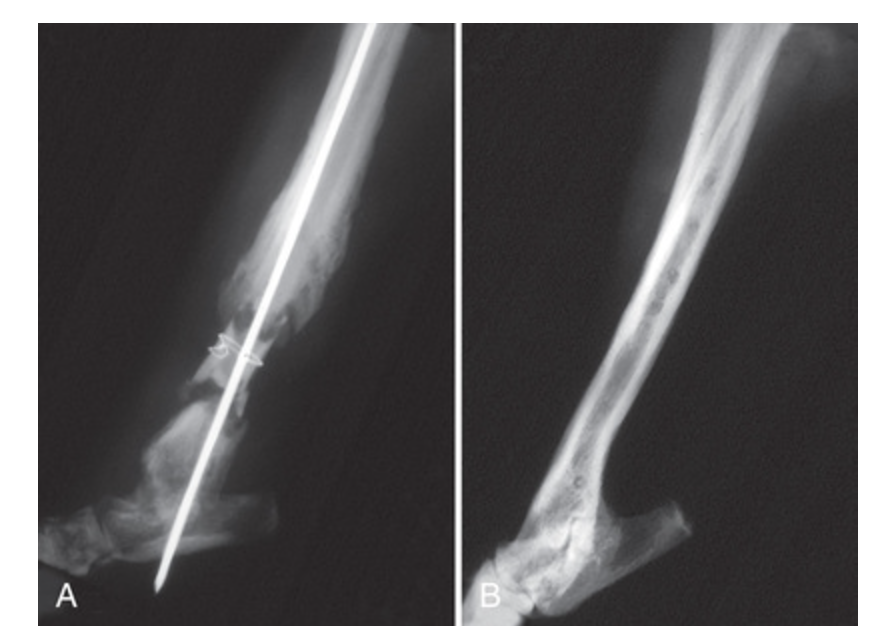

What type of non-union is depicted?

What are some radiographic changes associated with post-traumatic osteomyelitis?

A

Cortical resorption, periosteal proliferation, loss of trabecular markings +/- sequestrum and involucrum